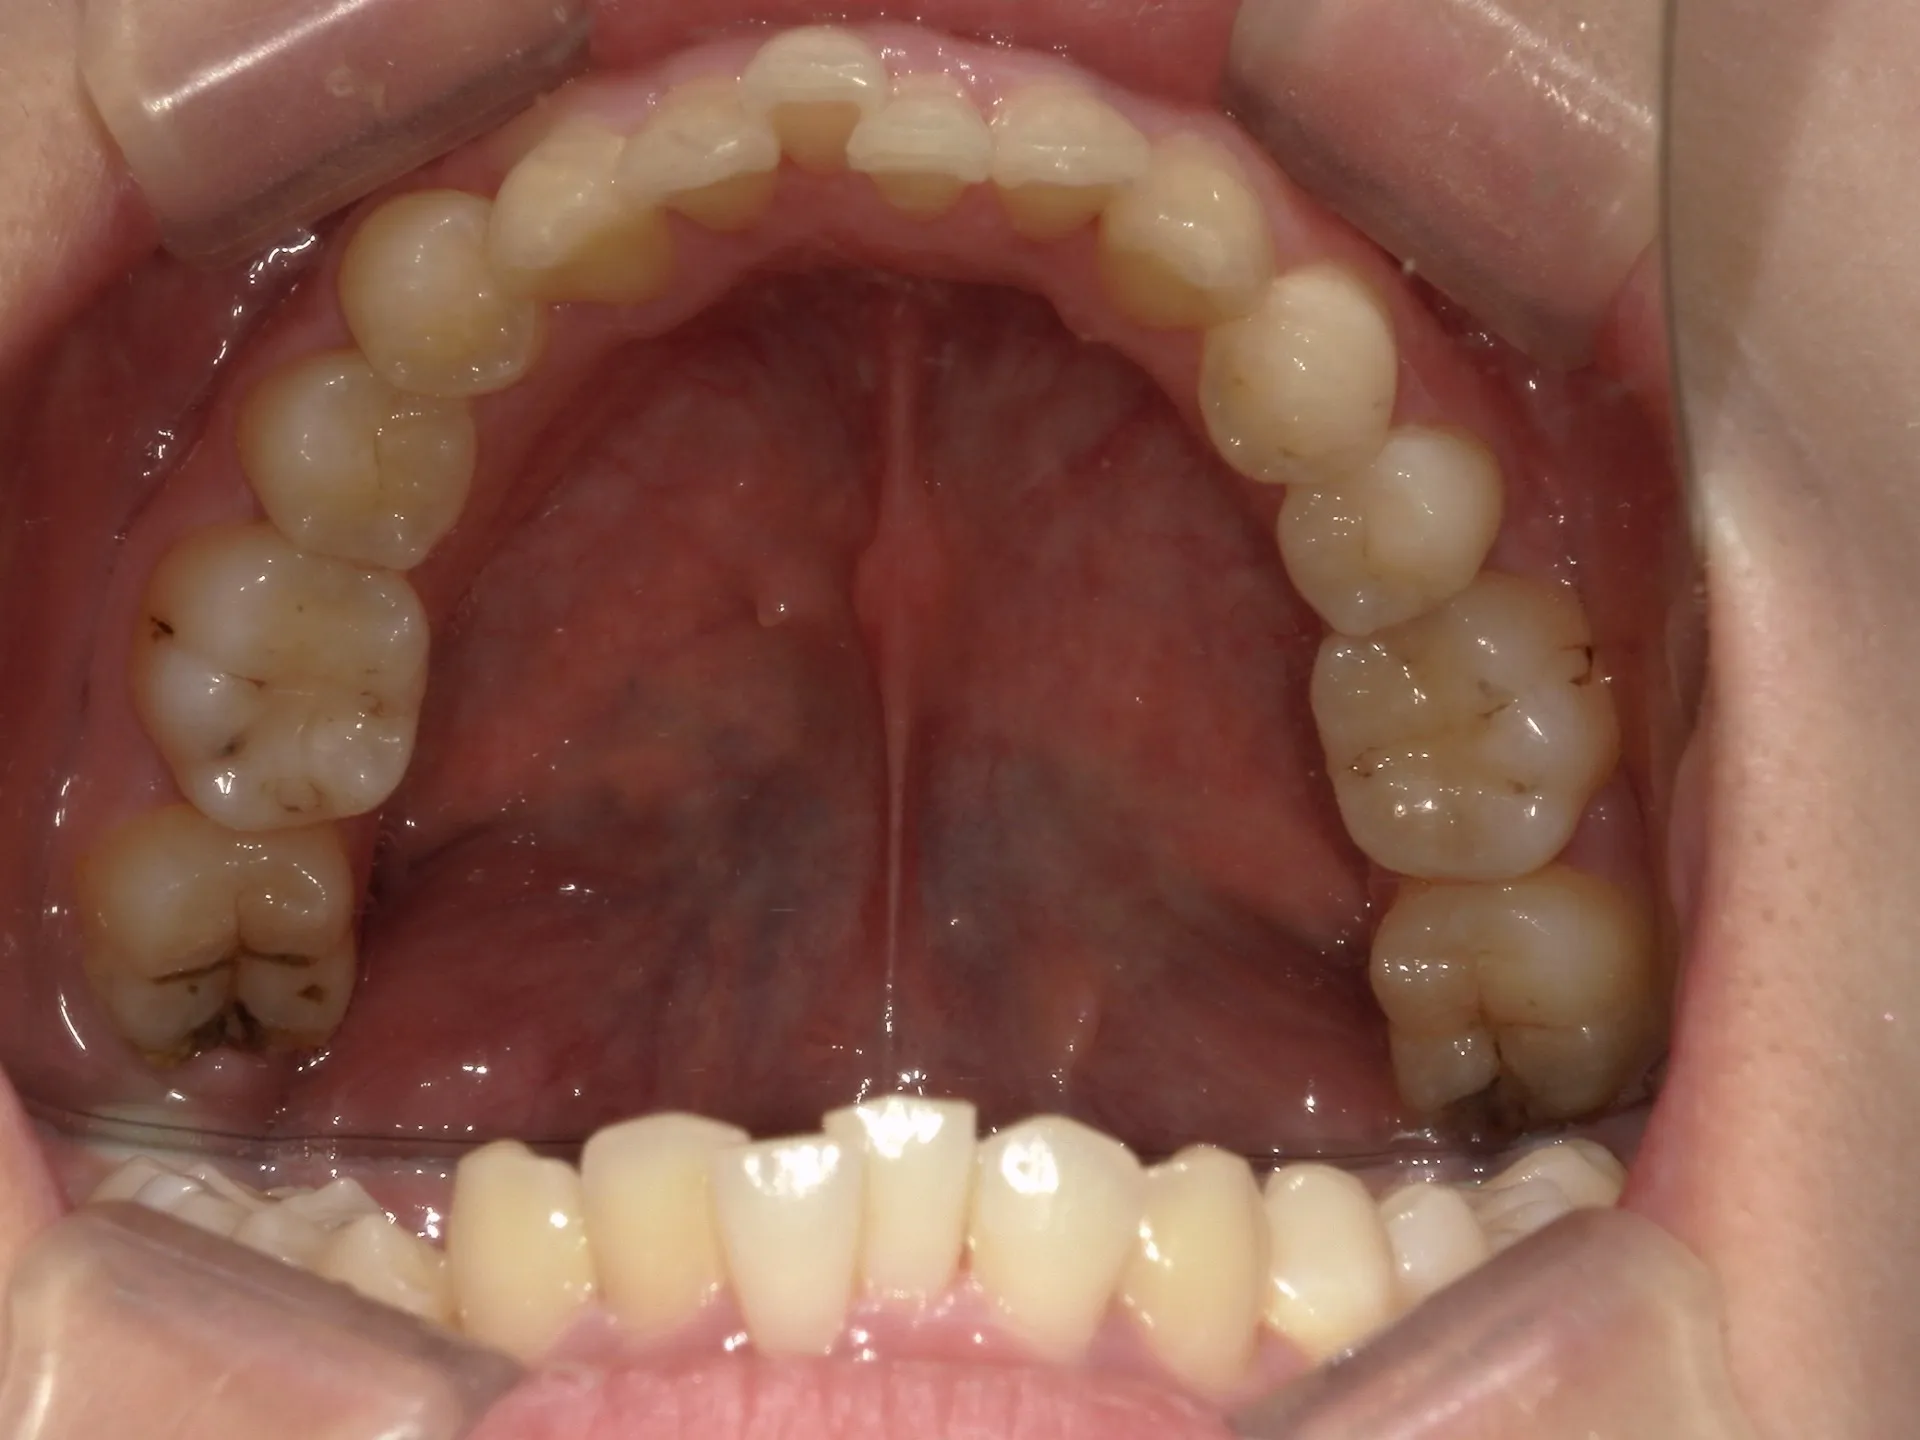

今回はマウスピース矯正(インビザライン)で前歯の出っ張りを治したケースをご紹介いたします。

マウスピース矯正で前歯の出っ歯感を抑えることが可能で、このケースでは上の歯のみ2本の抜歯を行っています。